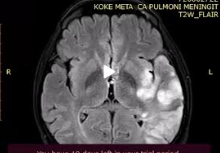

During hospitalization, the patient started having difficulties speaking leading to aphasia. Head CT resulted with multiple ischemic lesions.

Figure 4. Head CT showed multiple ischemic lesions.

Neurologist and neuro-surgeon consultation: Ischemic stroke due to malignant disease.

Oncologist consultation concluded Stage IV A Lung Cancer and suggested palliative care due to stroke complication. The patient left hospital and passed away two weeks later at his home.